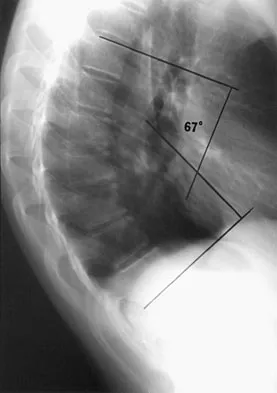

Question 70

Examination of a 13-year-old boy with asymptomatic poor posture reveals increased thoracic kyphosis that is fairly rigid and accentuates during forward bending. The neurologic examination is normal. Spinal radiographs show 10 degrees of scoliosis at Risser stage 2, and there is no evidence of spondylolisthesis. A standing lateral view of the thoracic spine is shown in Figure 41. The kyphosis corrects to 50 degrees. Management should consist of

Explanation